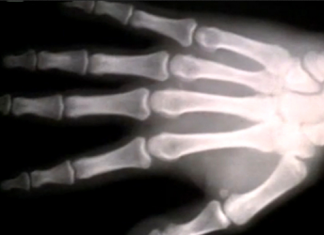

Медицинские новости